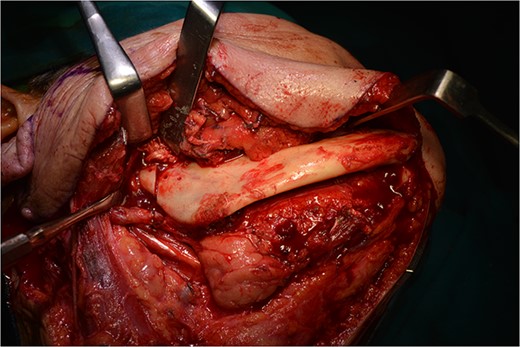

Operatively, after induction to general anaesthesia via orotracheal intubation, an extended submandibular incision to the right of the neck was performed and the mandible was revealed. The marginal branch of the facial nerve was recognized and protected. Following this, the double osteotomy of the mandible was performed in the parasymphysis—with preplating of two miniplates with four holes—and in the subcondylar area—with preplating of two miniplates with four holes (Figs 3 and 4). The mandibular ‘swing’ that was performed straight after that (Fig. 5) gave space for the dissection of the CCA and the bifurcation. All the branches were prepared, and the aneurysm was accessed (Fig. 6). The reconstruction was achieved by bypassing the aneurysm, trans-positioning of the right ECA and end-to-end anastomosis of the ECA with the healthy peripheral end of the ICA near the skull base, after the lignification of the peripheral end of the ECA and its smaller branches (Fig. 7). The anastomoses were checked for leakage (Fig. 8), the mandible was reduced and the easily fixated rigidly after preplating (Fig. 9).

All the branches of the carotid artery are demonstrated prepared, and the aneurysm is demonstrated.